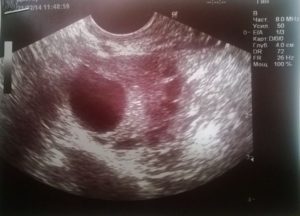

Но если оплодотворение все-таки произошло, первым делом специалист назначает ультразвуковую диагностику для определения размера и характера образования. Доброкачественные кисты лечения не требуют.

Женщине необходимо только принимать нужные витамины, регулярно сдавать анализы и делать УЗИ. Такое тщательное наблюдение позволяет контролировать развитие образования, и в случае озлокачествления, экстренно принимать меры.